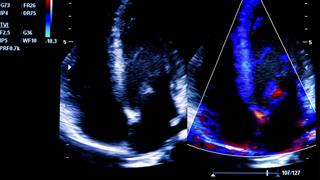

Το ΥΓΕΙΑ εισάγει για πρώτη φορά στην Ελλάδα, τον τετραδιάστατο ενδοκαρδιακό υπέρηχο

Διακαθετηριακές επεμβάσεις καρδιάς με χρήση της τρισδιάστατης και σε πραγματικό χρόνο ενδοκαρδιακής απεικόνισης, πραγματοποιήθηκαν για πρώτη φορά στην Ελλάδα, στο ΥΓΕΙΑ.